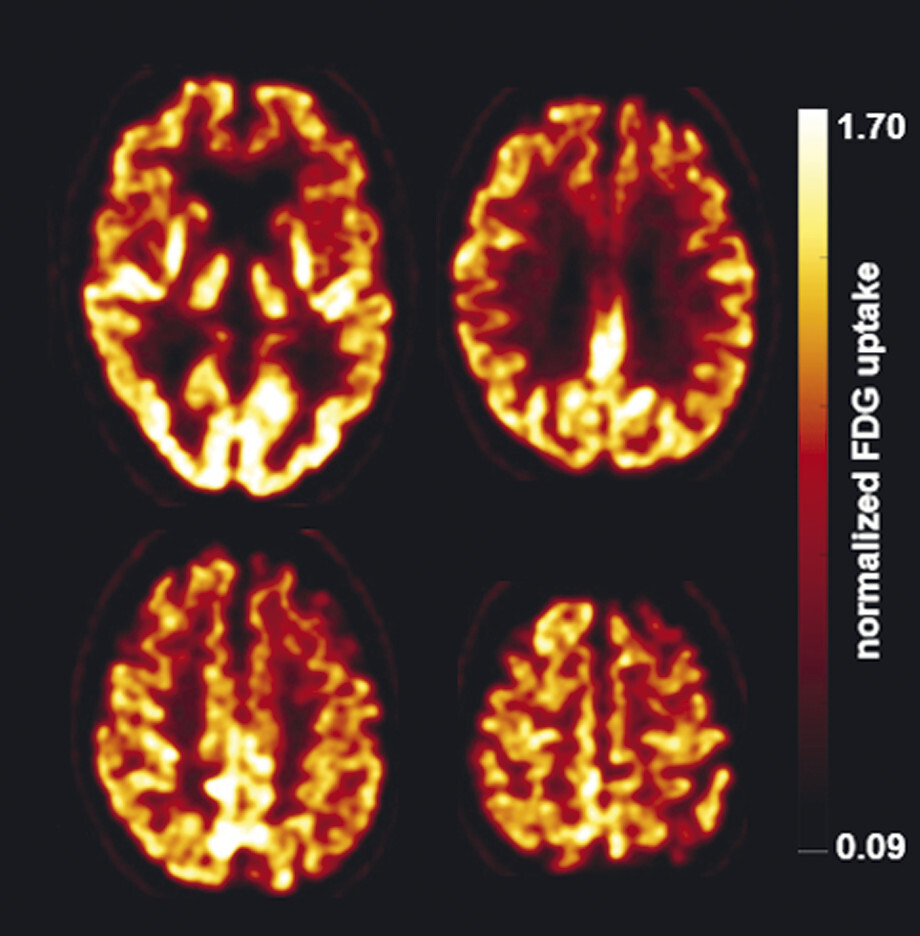

62-jähriger Mann mit über 3 Jahre zunehmender Bewegungsverlangsamung und unsicherem Gangbild. Die MP-RAGE-Aufnahmen zeigen eine deutliche Mittelhirnatrophie mit Kolibri- (a) und Mickey-Mouse-Zeichen (b). Das Mittelhirn/Pons-Verhältnis liegt mit 0,15 im pathologischen Bereich (Normalwert ca. 0,24). Die voxel- und regionenbasierte morphometrische Analyse (c) zeigt neben der Mittelhirnatrophie eine links-frontomesial betonte Atrophie, das FDG-PET (e) einen Hypometabolismus dieser Regionen. Dieses Muster ist typisch für eine sog. Tauopathie und unterstützt daher die Diagnose progressive supranukleäre Parese mit Richardson-Syndrom.

d Voxel- und regionenbasierte Analyse.

e FDG-PET. (mit freundlicher Genehmigung von Prof. Dr. Dr. P.T. Meyer, Klinik für Nuklearmedizin Uniklinik Freiburg)

61-jähriger Mann mit rechtsbetonter Gliedmaßenapraxie, sodass Schreiben und Zeichnen nicht mehr möglich sind. MP-RAGE-Aufnahmen (a–c) zeigen eine deutliche Atrophie der linken Großhirnhemisphäre mit Ausziehung vor allem der Cella media des linken Seitenventrikels. Die voxel- und regionenbasierte morphometrische Analyse (d) bestätigt die Atrophie mit Betonung des Parietallappens. Die FDG-PET (e) zeigt einen Hypometabolismus der linken Hemisphäre mit Beteiligung von Thalamus und Basalganglien. Klinische Symptomatik und Bildgebung sind passend für eine kortikobasale Degeneration.

d Voxel- und regionenbasierte morphometrische Analyse.